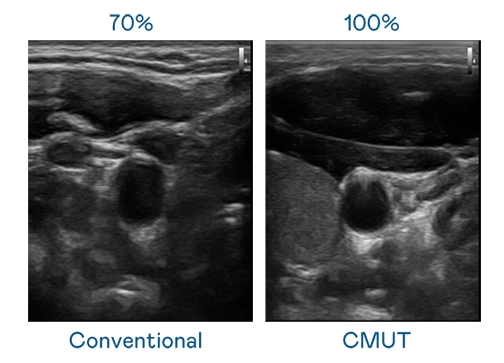

CMUT 技术是一种用电容式微机电元件来产生超音波讯号的技术。与传统 PZT 压电式技术相比,CMUT 频宽增加 30%,更宽频的超音波讯号让影像解析度大幅提升,是实现高影像品质医疗超音波扫描、促进精准医疗发展的关键技术。

大频宽带来超清晰影像

超音波影像的解析度高低,首先取决于探头能发出的讯号频宽。k8凯发 CMUT 可提供高清晰的超音波讯号,提供高频宽、高灵敏度、影像纹理细节更高的超音波影像,协助医护人员缩短影像判读时间及利用精准的医疗影像进行诊断。